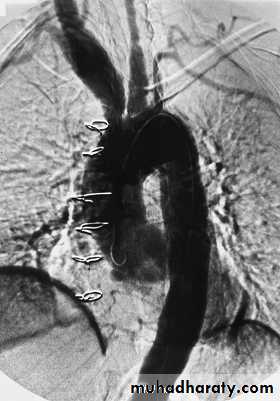

Angiogram showing multiple changes of Takayasu’s

arteritis including dilation of the aortic root (with surgical wires from previous aortic valve replacement), aneurysmal dilation of the innominate and right carotid arteries, and occlusion of the distal left common carotid artery